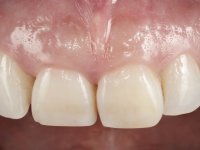

The proposed treatment results from the limitations imposed by the patient, who refused an orthodontical pull of the canine into the edntulous space, and was unwilling to extract the impacted canine and place an implant in the zone of 1.3. Thus, the confection of a Maryland Bridge was proposed, with a Zr infrastructure and two retainers. The mesial retainer would be bonded to the palatal face of the tooth 1.2 and the distal retainer was to be bonded to the palatal wall of tooth 1.4.

To define the dental zone to be covered by the Maryland bridge retainers, the patient was asked to perform maximum intercuspidation movements, and the contact points were marked with articular paper. Tooth preparation of the interproximal surfaces was made, to create a prosthetic insertion axis. It was sought that the mesio-distal diameter at the incisal level was equal to the diameter mesio-distal at the cervical level, that is to say, the interproximal walls were parallelized. Tooth preparation was done with fine grain diamond drills, and later polishing was done with abrasive discs. Color information was collected even before confection of the impression, to avoid dehydration of the arcade. Definitive impression was made using wash technique impression with silicone of heavy and regular consistency, both with fast setting, and a working plaster model was prepared in the lab. A laboratory scanner was used to scan the working model, and later, the infrastructure for the Maryland bridge was made using a CAD-CAM process. Ceramic was placed on this subframe. A ceramic adhesive was applied to the internal surface of the wings and connectors, which would enable bonding to the adjacent teeth. The adhesive bridge was bonded in the mouth following the conventional bonding technique. After bonding, the protrusion and laterality movements were carefully checked to avoid undesirable contacts.